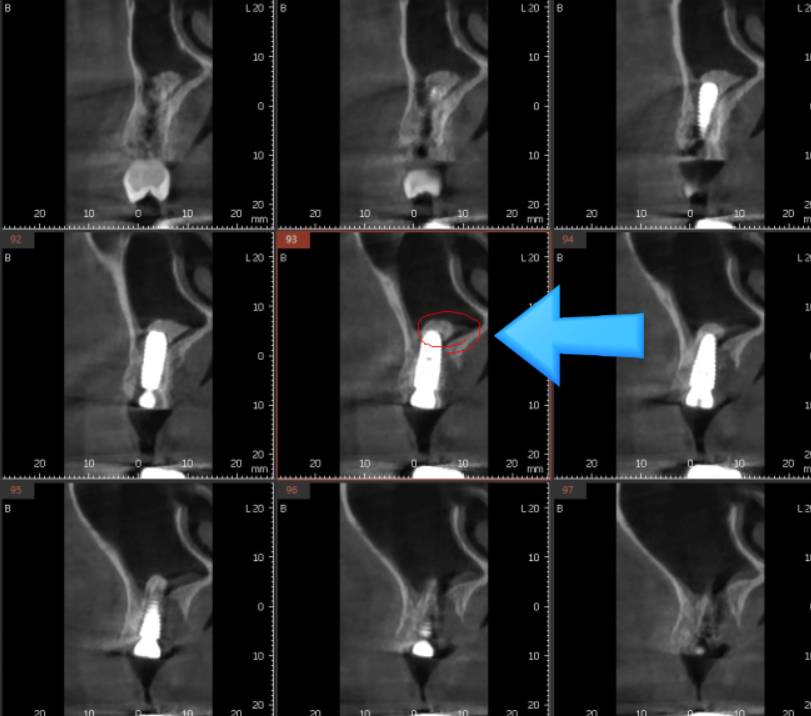

상악동을 들어올리고

뼈 이식을 한뒤

풍산동 임플란트가 필요했습니다.

24.03.30

풍산동 임플란트 상악동 올리고

뼈이식을 시행한 부위입니다.

돔 형태로 잘 이식이 되었습니다